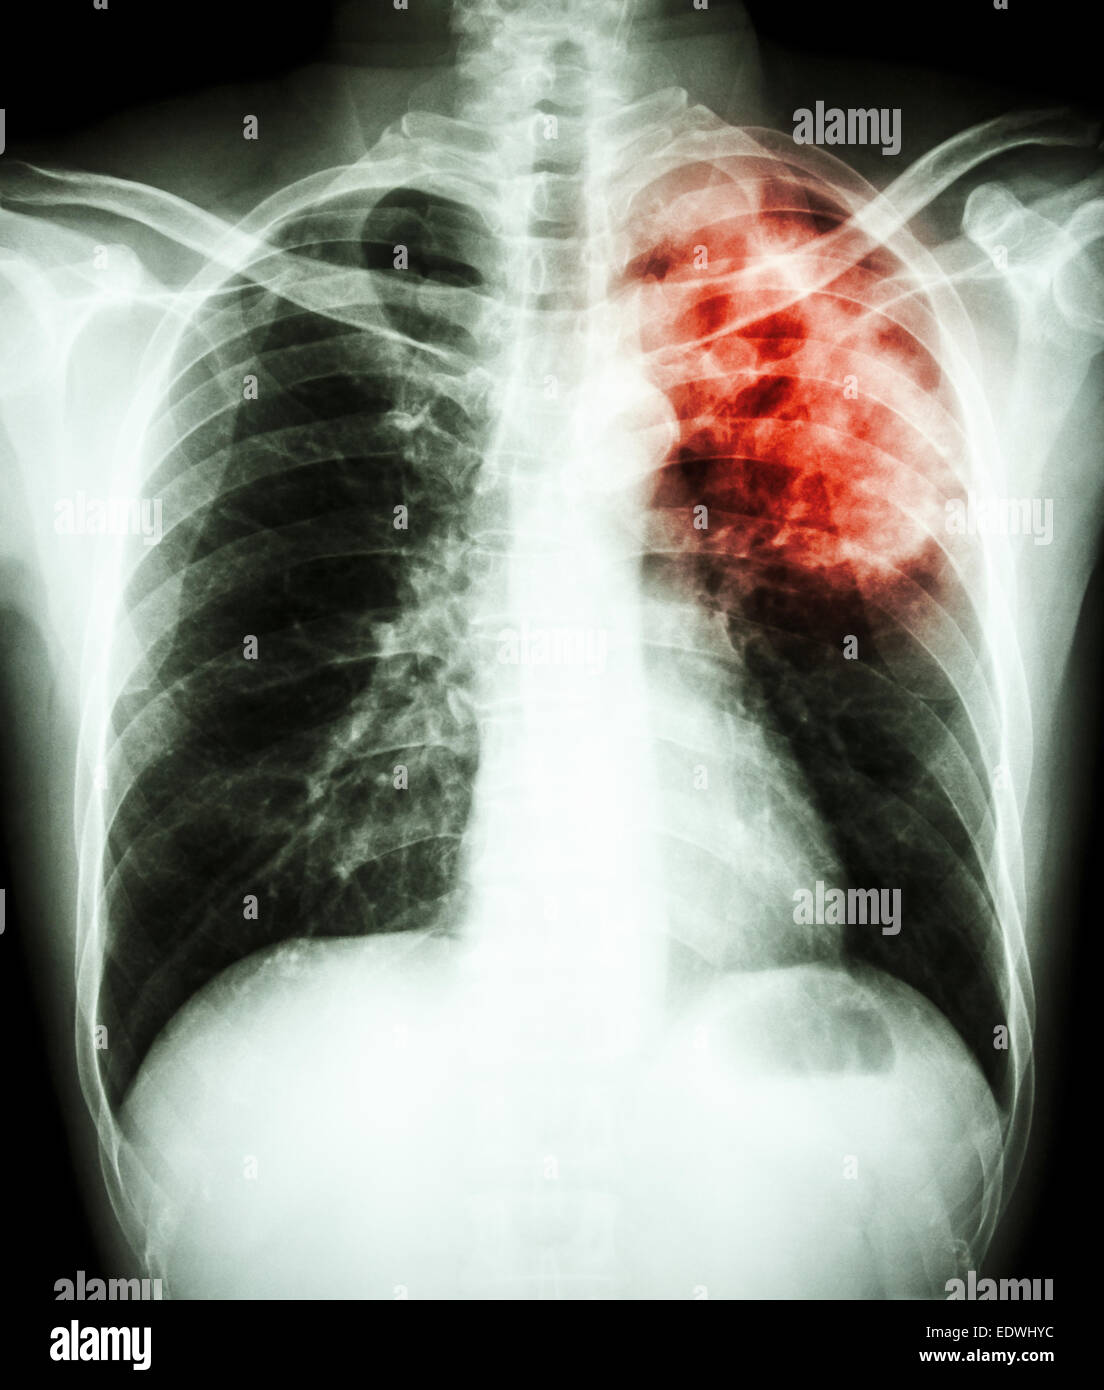

film chest xray show alveolar infiltrate at left upper lung due to Do Inflamed Lungs Show Up On Xray Pneumonitis happens when an irritating substance causes inflammation in the tiny air sacs called alveoli in your lungs. Lung nodules, in turn, are white specks in that black space, meaning there’s. Inflamed lung tissue makes it hard for. Images of your lungs can give an idea of where and how severe the inflammation is. Do Inflamed Lungs Show Up On Xray.